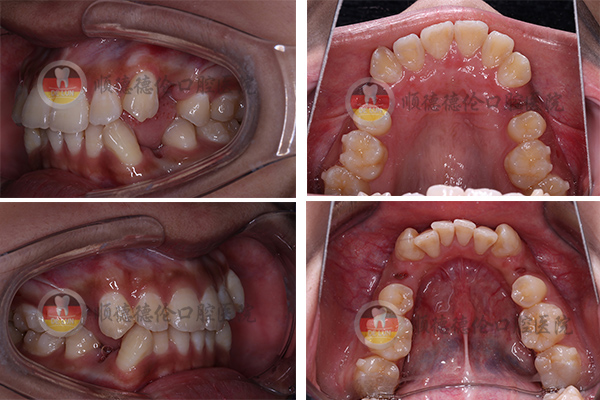

牙齒狀況:牙齒外突、擁擠、不整齊

3、拍口內(nèi)照

上下兩排牙齒共拔了8顆牙齒,為了變美我也是拼了(⊙o⊙)

我的方案是要拔牙的,說出來估計會嚇到別人,因為我拔了8顆,分三次拔完了,估計很少有人能夠理解,周圍不少朋友說我瘋了,我是想美想瘋了,哈哈哈……